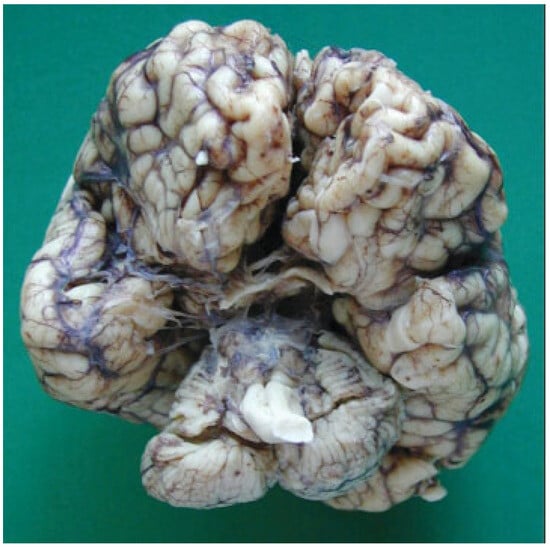

The autopsy study described a girl, 2 months and 20 days old, with karyotype (46,XX). She had frontonasal malformation (hypertelorism, broad nasal bridge, bifid nasal tip and anterior cranium), macrostomia, retrognathia, and bifid tongue. She also presented maxillomandibular bony fusion and fusion of the tongue to the palate and to the inferior lip by a hairy polyp (Figure 8), both corrected surgically. In the cranium, the sella turcica was broadened (Figure 9), with little prominence of the clinoid apophyses and with two cavities that contained two complete hypophyses with two infundibulums (Figure 10). The three cranial fossae were narrowed anteroposteriorly. The central nervous system (CNS) had both olfactory bulbs and corpus callosum agenesis (Figure 11 and Figure 12), anomalous morphology of the brain stem and spinal cord (Figure 13), and neuronal heterotopia in occipital white matter and leptomeningeal heterotopia.

Figure 11.

Olfactory bulbs agenesis.

Figure 12.

Corpus callosum agenesis.